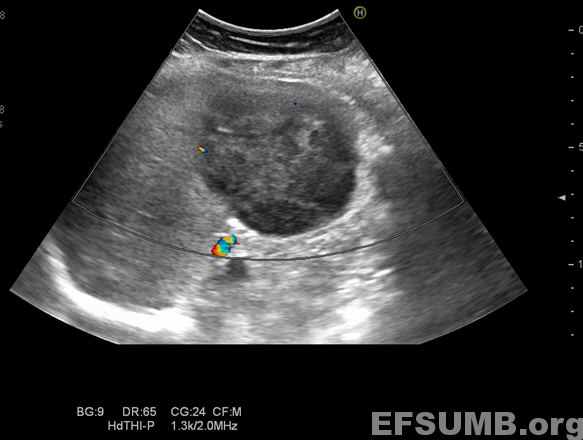

TITLE: Splenic lymphoma

B-mode ultrasound shows splenomegaly and a solid mass tumor: a large hypoechoic focal lesion located near the splenic hillum.